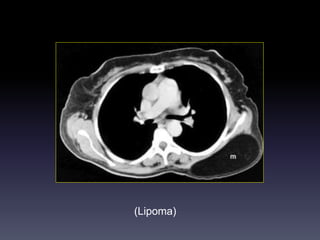

(Lipoma)

U XÖÔNG &PHAÀNMEÀM Hình CT -Huûy, bieán daïng xöông / Toån thöông phaàn meàm/ Xoùa lôùp môõ ngoøai maøng phoåi (+/- ) -Caàn khaûo saùt coù caûn quang. Vai troø CT -Ñaùnh giaù toát vò trí, möùc ñoä, lieân quan toån thöông vôùi caùc caáu truùc khaùc ngöïc (phoåi, maøng phoåi, trung thaát)